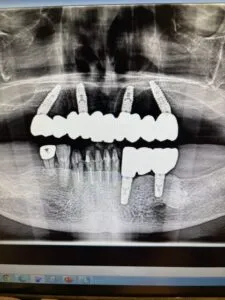

上顎はいわゆるオールイン4ってヤツですね。

インプラント4本入れて

その日のうちに仮歯を取り付けて

入れ歯とはサヨナラ、っていう。

入れ歯だと柔らかいものしか食べれなかったそうですが

なんでも咬めるようになってとても喜ばれてました。